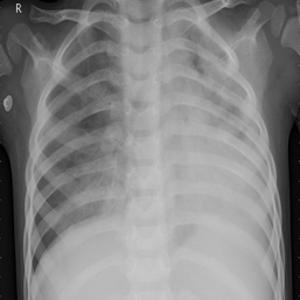

Ushbu platforma ko‘krak qafasi rentgen tasvirlarini sun’iy intellekt yordamida tahlil qilishga mo‘ljallangan bo‘lib, COVID-19, o‘pka fibrozlari, pnevmoniya hamda sog‘lom o‘pka to‘qimalarini to‘rt sinf bo‘yicha aniqlash uchun maxsus o‘qitilgan konvolyutsion neyron tarmoq (CNN) modelidan foydalanadi. Tizim tasvirni oldindan qayta ishlash, shovqindan tozalash va kontrastni kuchaytirish kabi raqamli algoritmlar asosida yuqori aniqlikdagi diagnostik xulosani taqdim etadi.